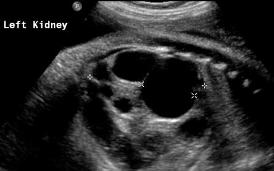

Above. Patient A. 37 weeks gestation. Transverse. Unilateral multi-cystic dysplastic kidney (MCDK). Multiple cysts of varying size and echogenic kidney.

Above. Patient A. 37 weeks gestation. Sagittal view. Unilateral MCDK. Multiple cysts of varying size and echogenic kidney. Contralateral kidney is normal.